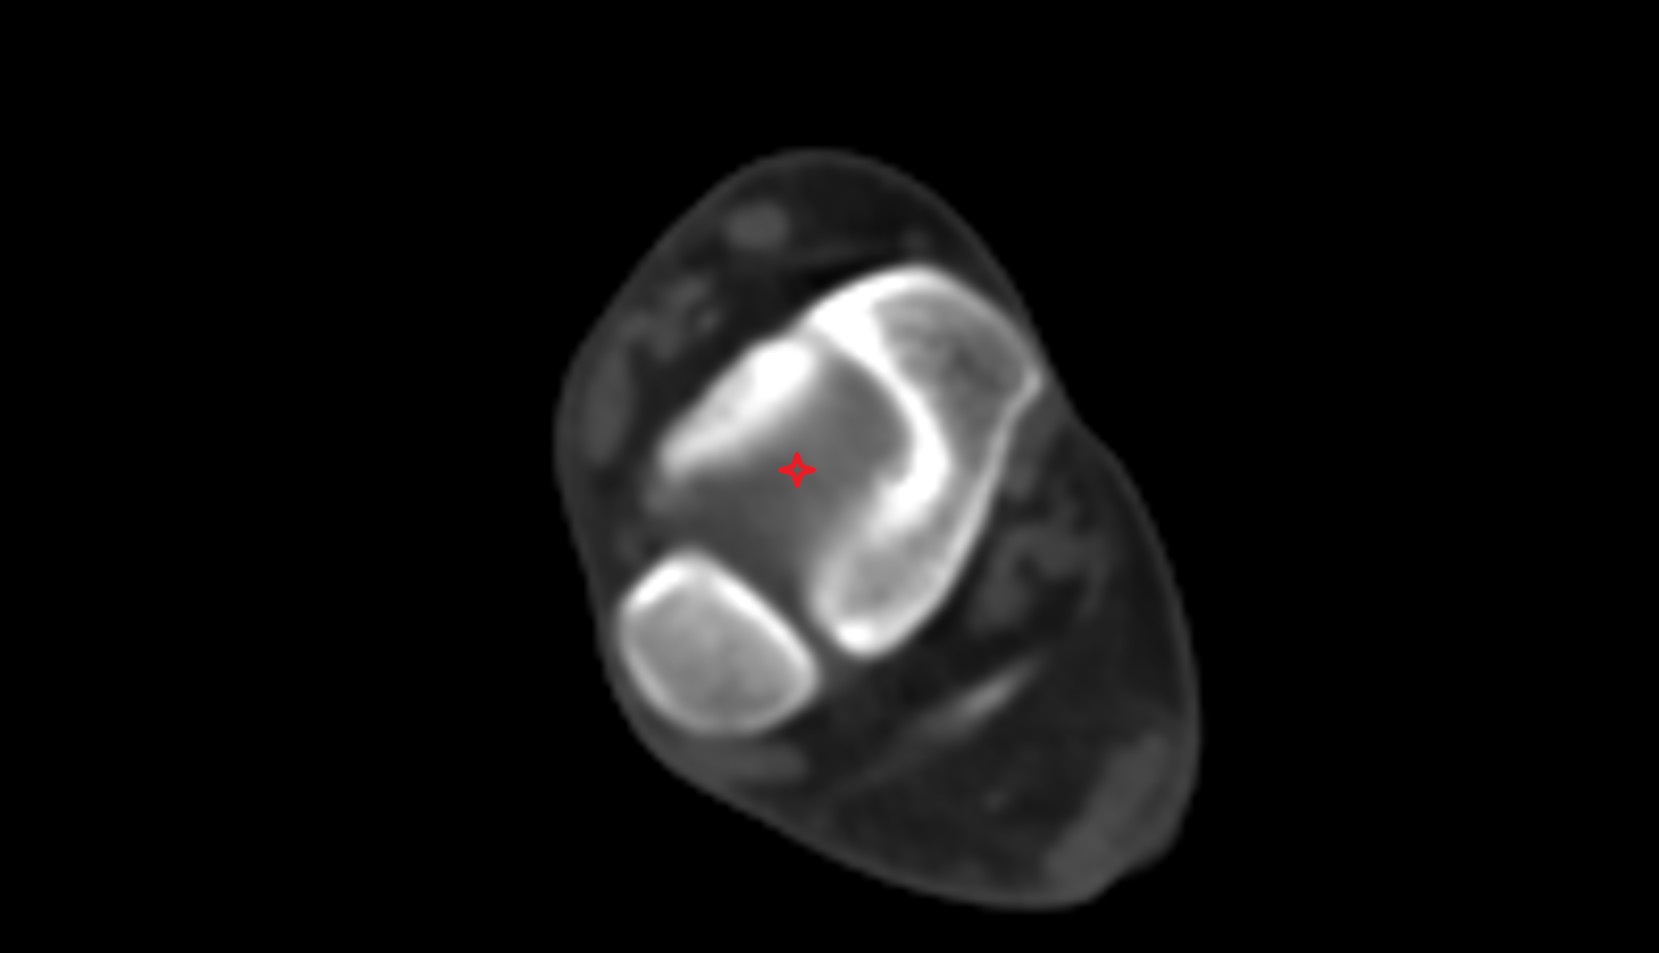

- Talus

- Body of talus

- Neck of talus

- Calcaneus

- Sustentaculum tali

- Ankle joint

- Talocalcaneal joint